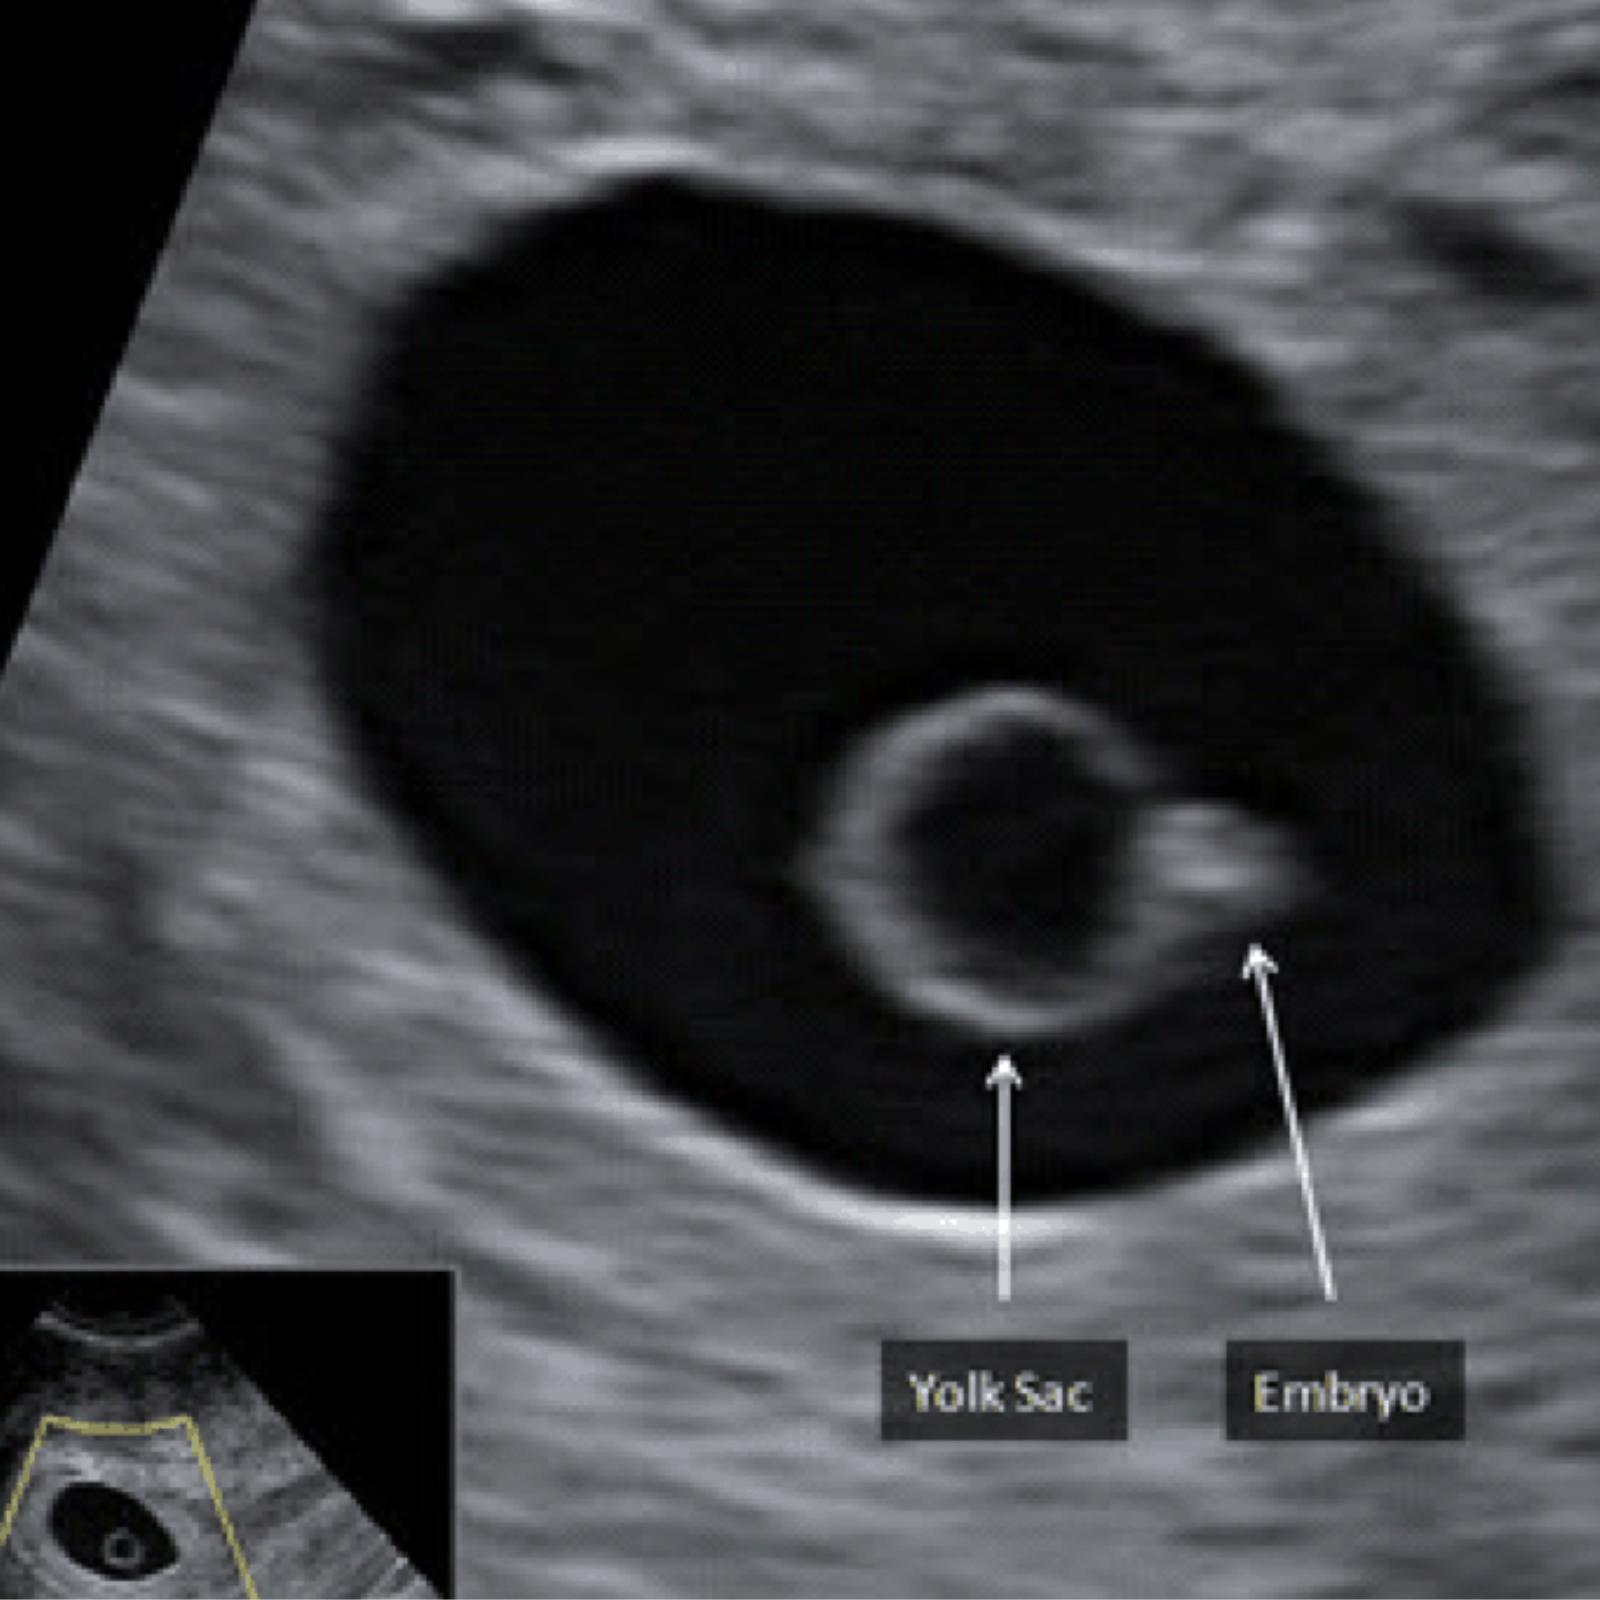

Ultrasound intervention is a modern, minimally invasive technique that uses high-frequency sound waves to guide precise diagnostic and therapeutic procedures. This advanced method allows doctors to visualize internal structures in real time, ensuring accuracy and safety during treatments.

At Sarvagya Diagnostic, we employ the latest ultrasound technology to perform guided interventions such as biopsies, fluid aspirations, and targeted therapeutic procedures. Our expert team combines skill with cutting-edge equipment to ensure maximum comfort, precision, and effective outcomes. With ultrasound intervention, we provide patients with safer alternatives to surgical methods, enabling faster recovery and better overall care.